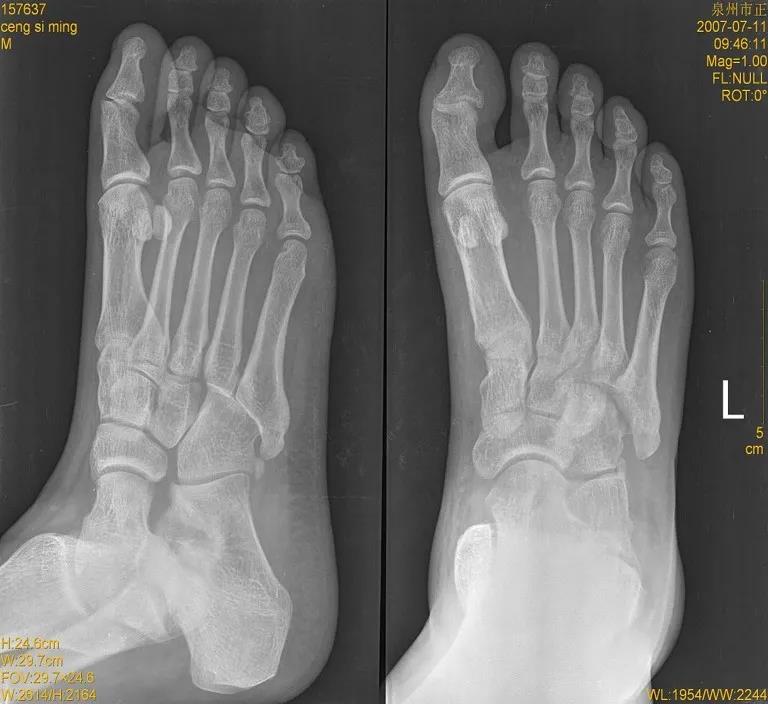

X线

儿童骨骺未闭

儿童正常骨骺